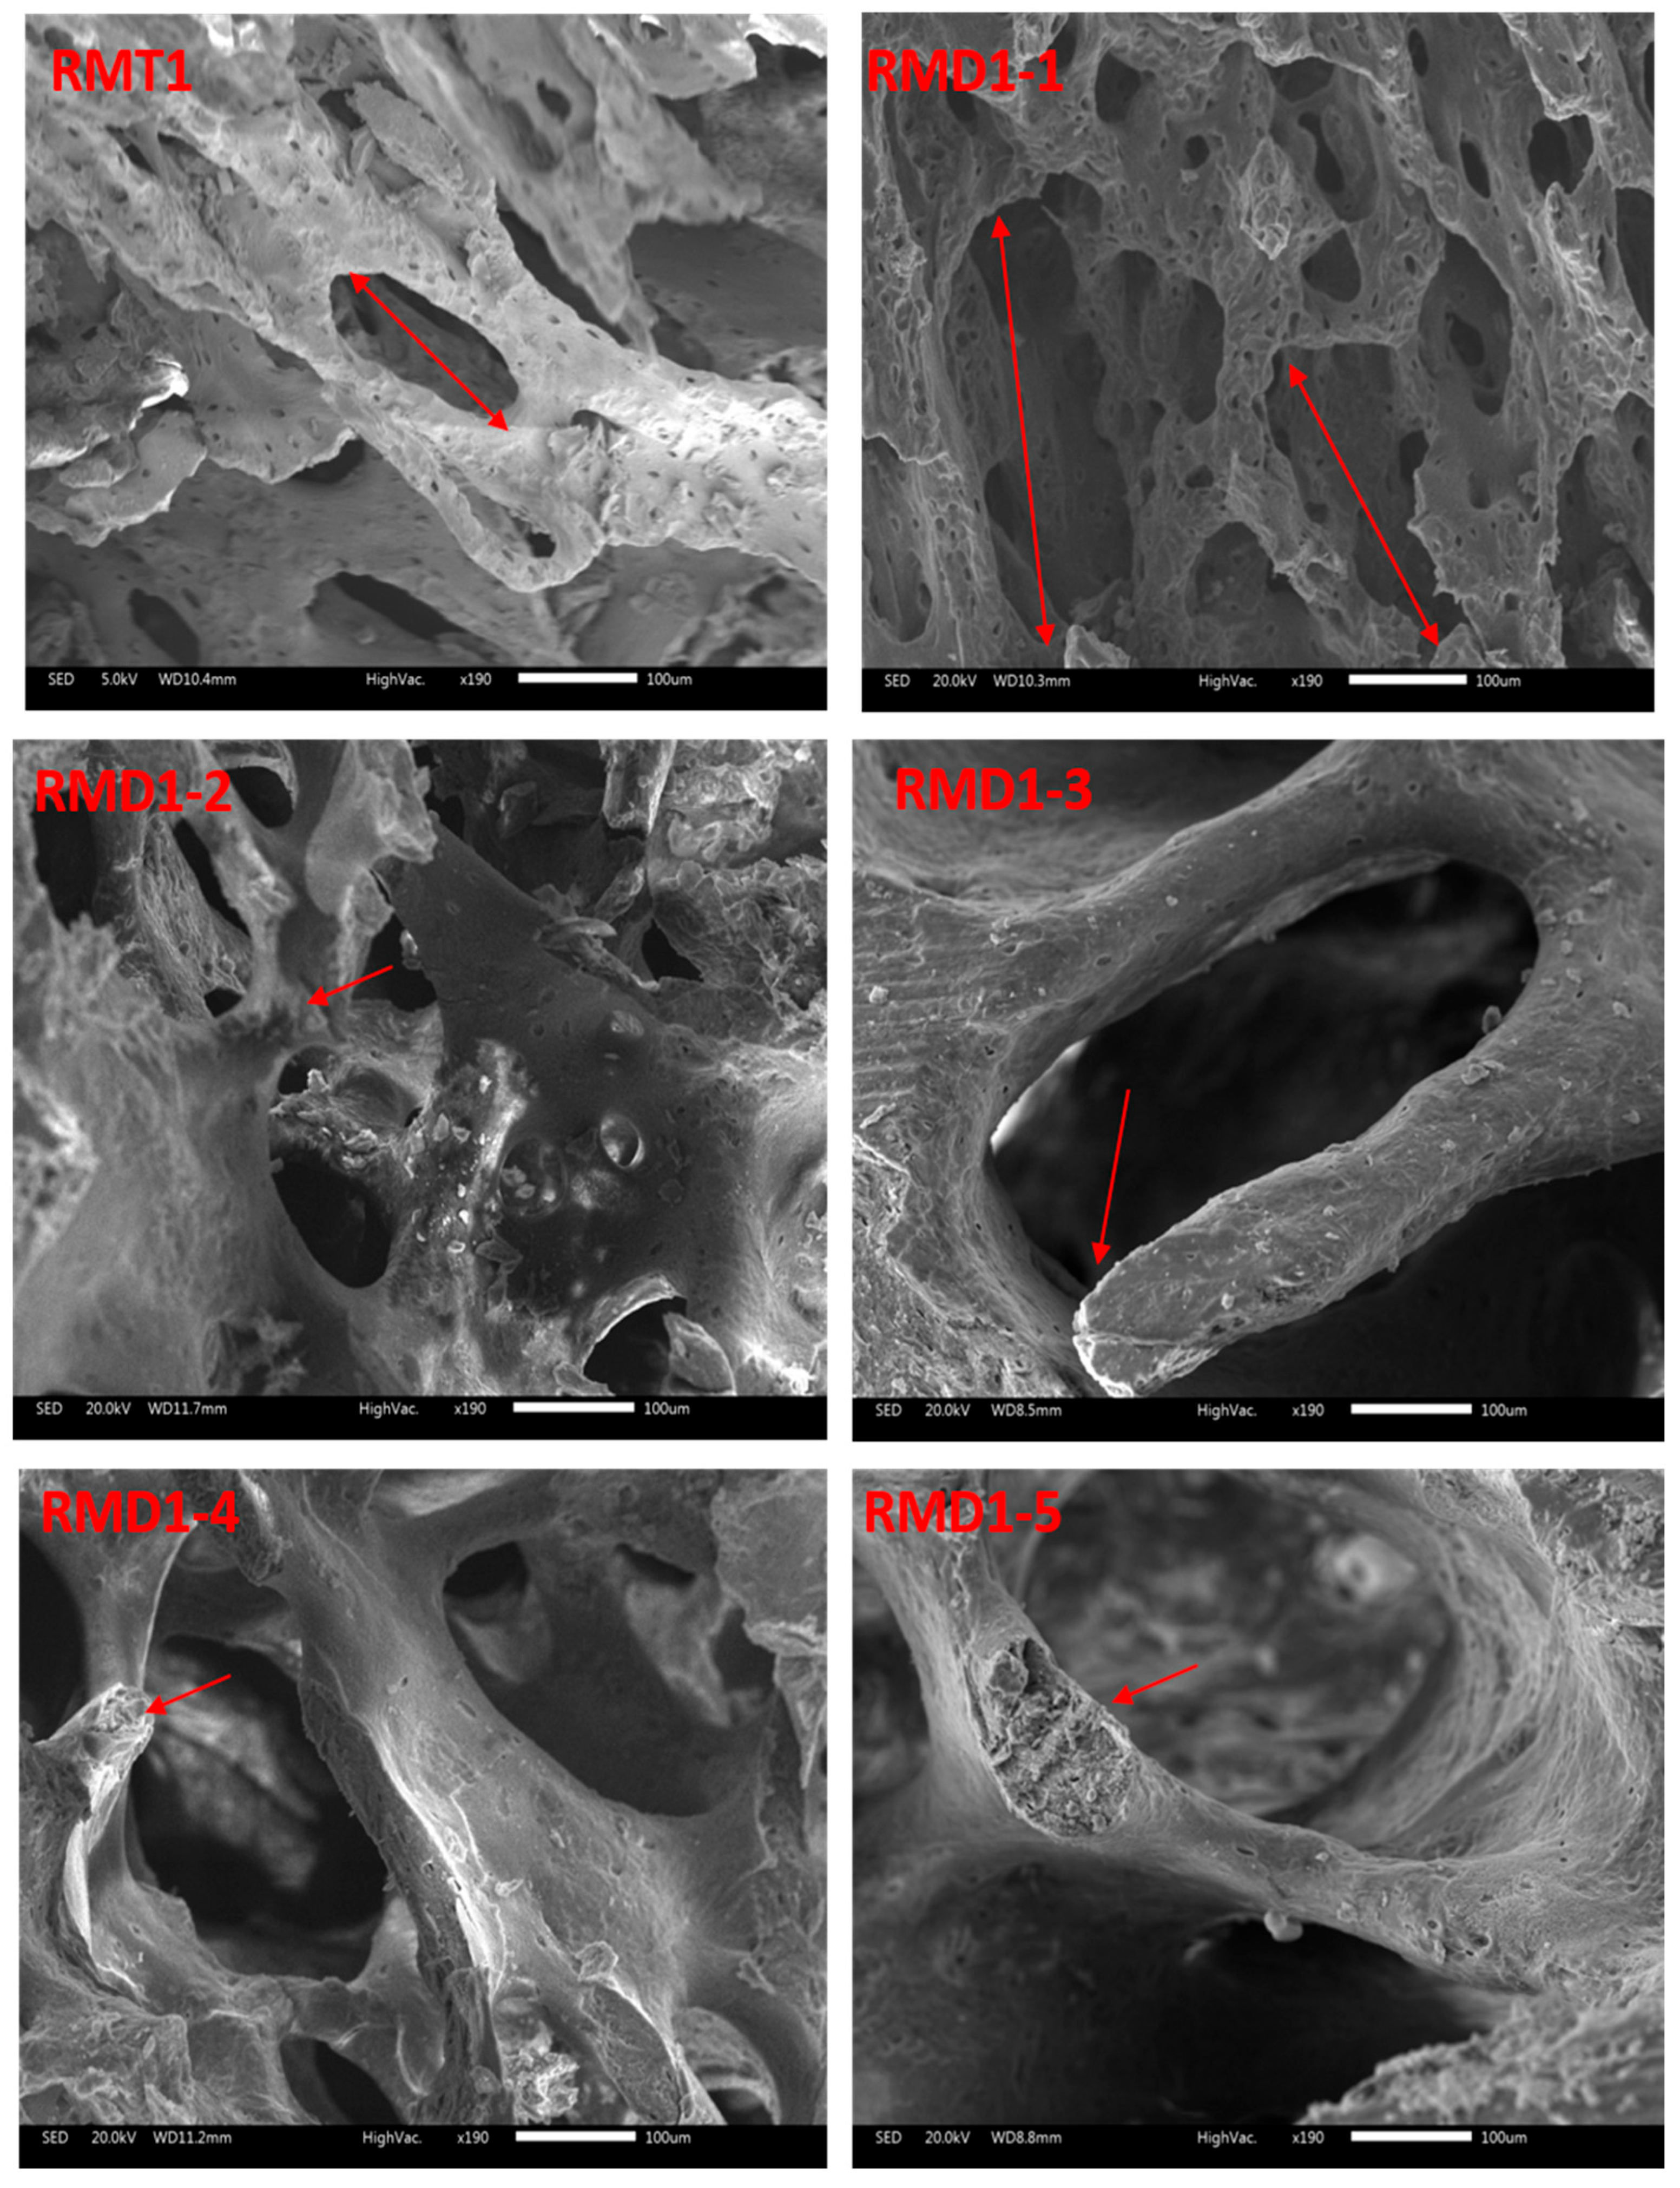

3.8. SEM Results